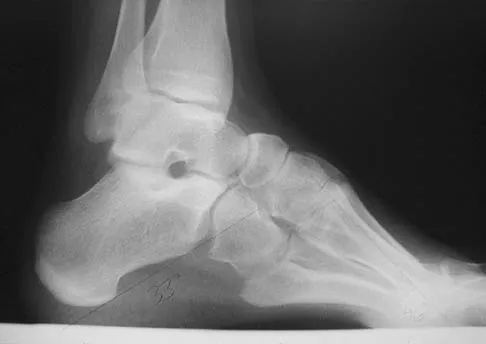

A 28-year-old man has had a 2-year history of progressive lateral ankle pain. History reveals that he underwent a triple arthrodesis at age 13 for a tarsal coalition. The pain has been refractory to braces, custom inserts, and nonsteroidal anti-inflammatory drugs. Weight-bearing radiographs of the ankle and foot are shown in Figures 3a through 3d. Surgical management should include which of the following?